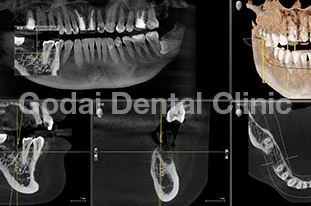

患者様は20代男性、虫歯の治療をしたいことと、歯並びを改善したいという主訴で来院されました。歯医者は10年以上ぶりですが、虫歯も歯並びもしっかり治したいという希望を持っていました。久しぶりの歯医者ということもあり、まずは歯磨きの仕方から改善していきました。歯垢をブラッシングで除去できるようになったところで、虫歯の治療を開始しました。歯並びが悪いこともあり、多くの歯に虫歯が見つかりました。患者様の年齢と歯質の保存を優先し虫歯の治療はコンポジットレジン修復を行いました。また下の親知らずが横向きに生えていたため、左右の親知らずの抜歯を矯正前に行いました。

歯ブラシの改善と虫歯の治療、親知らずの抜歯が終わったところで、矯正治療へ移行しました。患者様は健康な歯を抜きたくないという希望を持っていたので非抜歯の治療計画を立てました。まずは上下顎ともに拡大装置を用い歯列の拡大を行いました。その後、アライナーを使ったインビザライン矯正治療へ移行し、歯並びの修正と咬み合せの確立を行いました。拡大装置を使っている際は、口内炎や話しずらさなどがあったそうですが、インビザライン治療に移行してからは痛みも話しずらさもなくなり快適に過ごせたそうです。もともと多くの虫歯があったため矯正中の虫歯が心配でしたが、インビザライン矯正治療を選択したことで、新しい虫歯を作らずに治療を終えることができました。

歯並びを改善したい場合でも、歯磨きの確立、虫歯の治療、親知らずの抜歯など矯正前に治療が必要な場合もあります。ただ矯正前の治療をしっかりと行うことで、矯正治療の結果がより良いものになりますし、治療もスムーズに進みます。最終的に患者様にとって最善の治療になるよう心がけて治療を行っています。口の中が心配な方は、いつでもご相談ください。

治療前1

治療後1

治療前2

治療後2

治療前3

治療後3

治療前3

治療後3

治療前3

治療後3